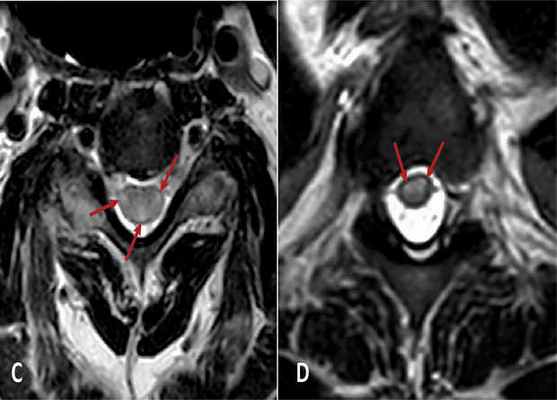

Аксиальный срез на уровне шейного (С) и грудного (D) отделов. Стрелочками показаны участки гиперинтенсивности.

Diógenes Harris et al. / Frontiers in Immunology, 2021

Неврологи Панамской больницы под руководством Диогенеса Харриса (Diógenes Harris) описали случай возникновения острого поперечного миелита после коронавирусной инфекции у пожилого пациента. К ним в отделение доставили мужчину 72 лет с жалобами на задержку мочеиспускания. Спустя три дня у него развилась слабость в конечностях. Пациенту сделали два теста на COVID-19, но они оказались негативными. В плазме у пациента определялись антитела IgG и IgM к коронавирусу, что свидетельствует о недавно перенесенной инфекции, которая протекала у пациента без симптомов. Лабораторные показатели были в норме, кроме повышения содержания С-реактивного белка и СОЭ (скорости оседания эритроцитов), что говорит о воспалении в организме. На МРТ спинного мозга наблюдалось легкое увеличение и припухлость шейного и грудного отделов спинного мозга с диффузной гиперинтенсивностью. Пациенту поставили диагноз острого поперечного миелита и назначили лечение преднизалоном, эноксапарином и гамма-глобулином. Впоследствии у него восстановилась работоспособность верхних конечностей, но нарушения в работе мочевого пузыря и нижних конечностей остались неизменными.